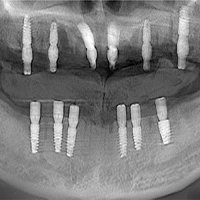

全口修复病例